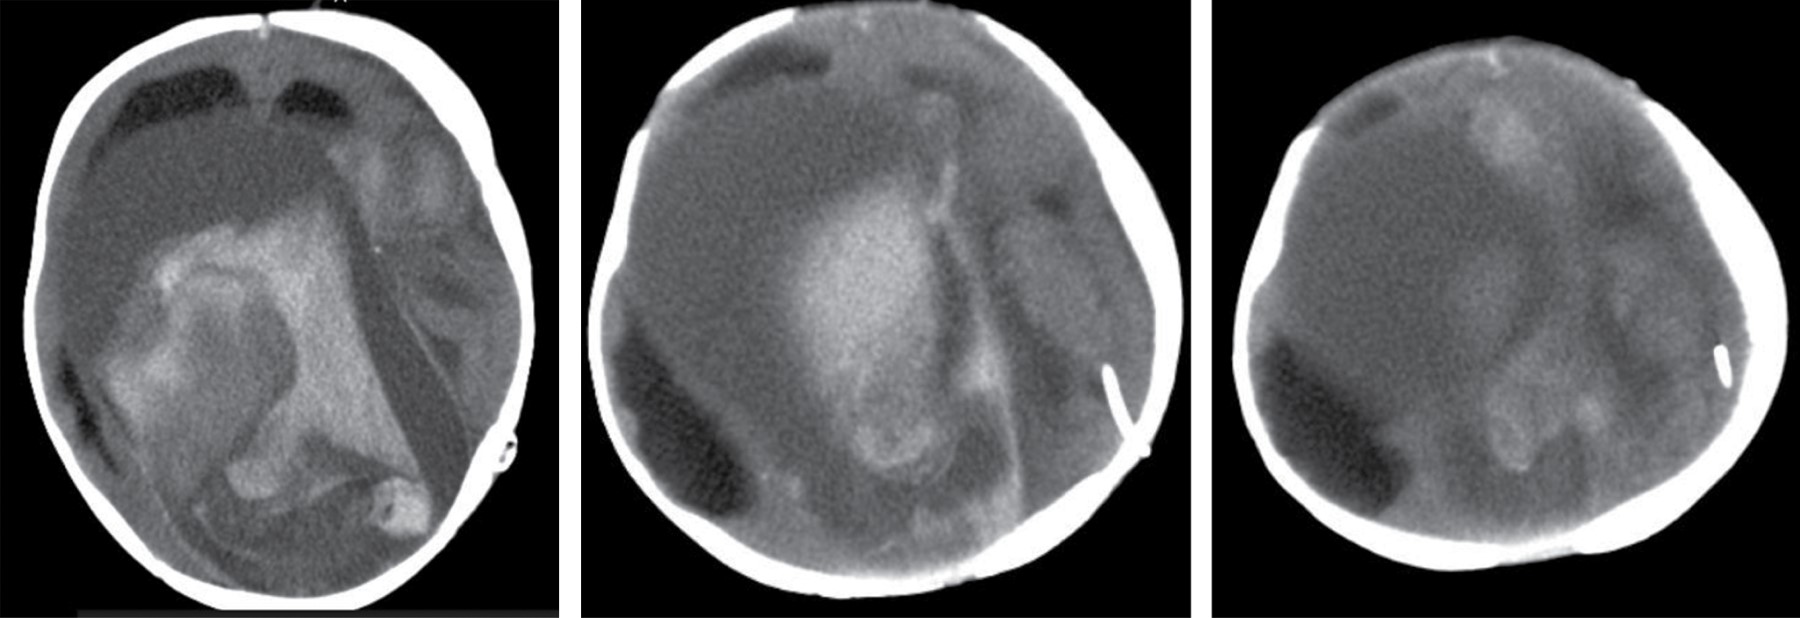

El paciente nació a las 37 SDG mediante cesárea electiva, con buena adaptación neonatal, así como peso y talla normales. Se decidió su trasladó a la Unidad de Cuidados Intensivos Neonatales (UCIN). En la exploración física se encontró macrocefalia, fontanela anterior amplia y normotensa, malformación vascular cutánea de la región frontal izquierda extendida a párpado superior ipsilateral, puente nasal amplio, ausencia de soplos cardiacos, acrocianosis, y con reflejos primarios presentes. Por ecocardiografía Doppler color se detectó hipertensión arterial pulmonar grave, confirmando la dilatación de cavidades derechas y disfunción diastólica del ventrículo derecho. La tomografía de cráneo simple evidenció la MAVG (Figura 2).

Al sexto día de vida se trasladó a sala general con oxígeno. Se decidió iniciar espironolactona. Al octavo día de vida, una angiorresonancia magnética cerebral confirmó el hallazgo tomográfico, con una clasificación de Yasargil tipo II (Figura 3). Fue valorado por neurocirugía pediátrica, planteando manejo endovascular de manera programada, por lo que se egresó a su domicilio.

Figura 2

Figura 3